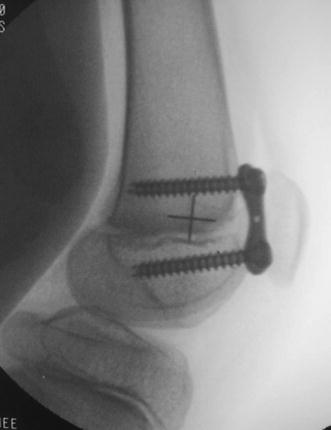

Under tourniquet control, using fluoroscopic guidance, the distal femoral physis was identified; this is best observed in the lateral, cross-table projection. Two incisions about 3 cm long were made on either side of the patella, centered over the physis. The capsule and synovium were opened, the femoral sulcus visualized, and the plates placed just outside the articular portion of the joint surface. The central hole of the 8-plate was slipped over the Keith needle, which was inserted into the physis. Two 1.6-mm guide wires were then passed through the proximal and distal holes of the plate under fluoroscopic guidance, taking care not to violate the physis or the joint. The cortex was drilled (5 mm), and self-tapping, cannulated, 24-mm screws were inserted. Upon removal of the guide pins, the screws were further tightened to countersink them within the plate. The screws need not be parallel, and the implants were intracapsular, but not on the articular surface (Fig. 2). The wound was closed, soft dressing applied, and the patient was allowed ambulation as tolerated. Follow-up films were taken at 4 weeks to assure the position and integrity of the plates (Fig. 3). The patients were followed at 3–6 month intervals. When full passive extension was achieved, the gait analysis study and physical examination were repeated. Within 1 month following the gait study, plates were removed (average plate insertion time 15.07 months, range 11–23 months).

Fig. 2.

Intraoperative fluoroscopic view demonstrating the positioning of the anterior 8-plate (subject 1), one is placed on each side of the patello-femoral sulcus. They are intracapsular but non-articular